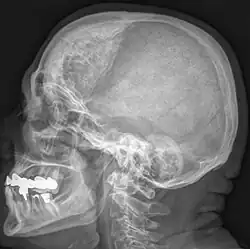

Die Hyperostosis frontalis interna ist eine häufige, gutartige Verdickung der Schädelkalotte im Bereich des Stirnbeins zur Innenseite hin. Die Hyperostose findet sich vornehmlich bei Frauen in und nach den Wechseljahren und bleibt in der Regel symptomlos. Meist wird sie als Zufallsbefund bei einer Röntgenaufnahme oder Computertomographie des Schädels entdeckt. Wichtig ist der Befund lediglich zur Abgrenzung eventueller Erkrankungen, siehe Differentialdiagnostik.

Die Abgrenzung in der Röntgenuntersuchung zu anderen Erkrankungen wie z. B. Knochenmetastasen oder Morbus Paget gelingt in der Regel durch die symmetrische Verteilung, die typische Ausbreitung rein frontal und nur nach innen, so wie den rein hyperostotischen und nicht destruktiven Charakter leicht.